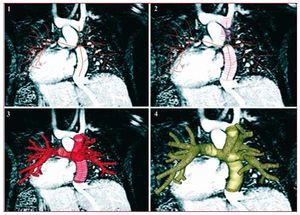

Models are typically constructed based on MRI or CT image data using segmentation methods.23 In methods pioneered by Taylor, patient-specific models are constructed in the following steps: a) paths are defined that run down the center of the vessels of interest; b) the vessel lumen is defined at fixed intervals along each vessel (segmented); c) the vessel portions between the 2D segmentations are interpolated and joined using custom software to create a 3D solid model of the desired vasculature (lofted); and d) a mesh is generated to represent the solid model for use in the finite element flow solver. The steps in model construction are illustrated in Figure 1 for a typical Fontan patient.

Figure 1.Four steps involved in model construction (patient D): (1) creation of vessel paths, (2) segmentation, (3) lofting, and (4) mesh generation. The image is displayed in the posterior-anterior view for ease of viewing. From Marsden et al.16